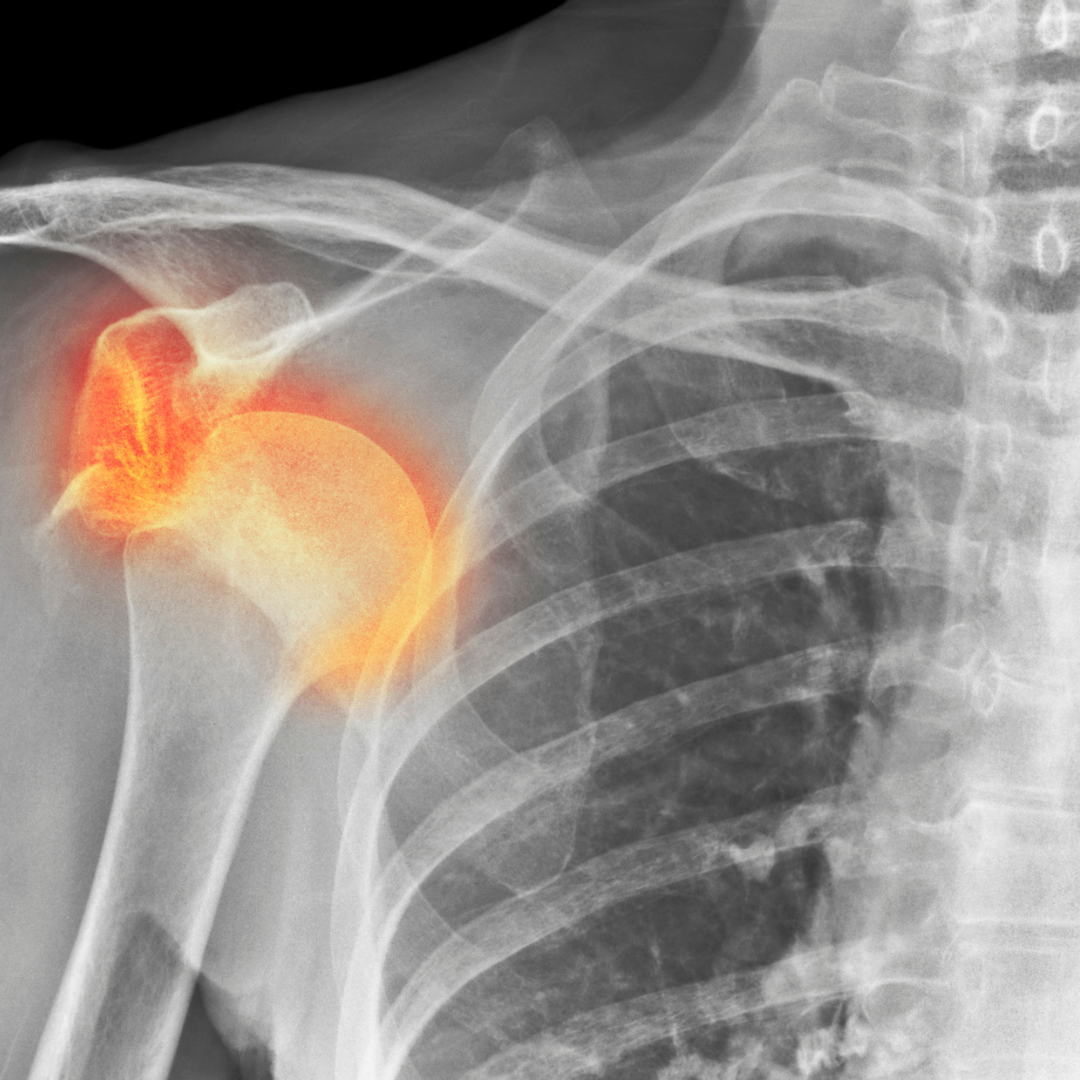

Izpah ramena

Kaj morate vedeti?

Izpah ramena nastane, ko glava nadlahtnice zdrsne iz sklepne jamice, kar povzroči izgubo stabilnosti sklepa. To je ena najpogostejših dislokacij v telesu zaradi velike gibljivosti ramenskega sklepa. Do izpaha pride pri močnem udarcu, nenadnem sunku ali padcu na iztegnjeno roko.

Simptomi pri poškodbi:

• Nenadna, močna bolečina v rami

• Očitna deformacija ali sprememba oblike ramenskega sklepa

• Nezmožnost premikanja roke v prizadetem sklepu

• Oteklina in podplutbe okoli rame

• Občutek nestabilnosti ali ponavljajočih se izpahov pri določenih gibih

Zdravljenje

Prva pomoč vključuje imobilizacijo roke in takojšnjo zdravniško oskrbo. Izpah je treba čim prej reponirati (vrniti kost v sklep), kar običajno opravi zdravnik. Po reponaciji sledi obdobje imobilizacije in postopna rehabilitacija za krepitev mišic okoli ramenskega sklepa. Pri ponavljajočih se izpahih ali poškodbah vezi je lahko potrebna kirurška stabilizacija sklepa. Dolgotrajna fizioterapija pomaga obnoviti moč in gibljivost ter preprečiti ponovne izpahe.

Preventivni ukrepi

Krepitev mišic rotatorne manšete in stabilizatorjev ramena zmanjšuje tveganje za izpah. Pri športih s povečanim tveganjem za poškodbe je priporočljivo uporabljati zaščitne opornice ali tehnike za stabilizacijo rame. Pravilna tehnika gibanja in izogibanje nenadnim sunkovitim gibom lahko preprečita ponovitev izpaha.

Izpah rame